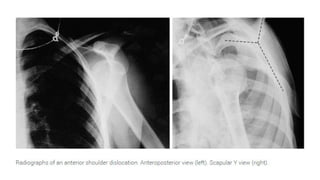

Radiological Confirmation of Shoulder Dislocation

Significance of X-ray Imaging:

● X-ray imaging plays a critical role in confirming

shoulder dislocation and identifying associated

fractures.

Importance:

● X-rays provide essential diagnostic information

for healthcare professionals managing shoulder

injuries.

● They help determine the type of dislocation,

assess fracture patterns, and guide treatment

decisions.

Specific Features to Look For:

1. Position of Humeral Head:

● Examine the position of the humeral head relative to the

glenoid fossa.

● In anterior shoulder dislocation, the humeral head will

typically appear displaced anteriorly from its normal

anatomical position within the glenoid fossa.

● In posterior dislocation, the humeral head may be displaced

posteriorly.